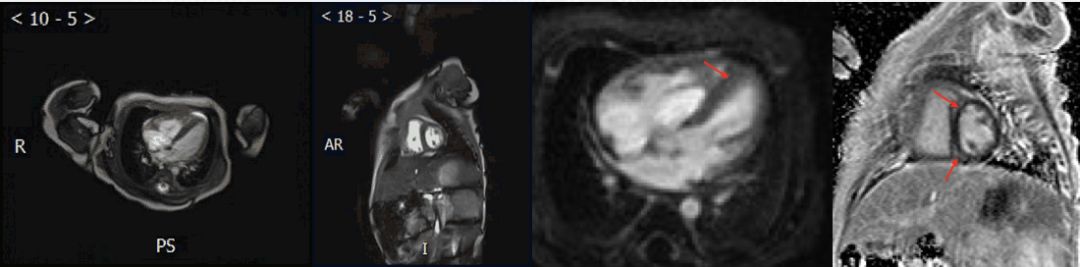

➤ 本病例3例患儿在初始评估后均行CMR检查

✦ Case 1

CMR:右心房、室增大,左心房前后经13.7mm,右心房前后径16.5mm,右心室舒张末期内径约18.3mm,EF 58%。右心室及间隔壁可见室壁增厚,间隔壁可见摆动。

CMR:左心室增大,左心室舒张末期内径59.4mm,EF 13.3%

电影MRI:左心室室壁运动减低,收缩功能下降。心包内见少量液性信号影。

心肌延迟强化成像:中央段-心尖段下壁及前壁可见心肌中层线样高信号影

✦ Case 3

CMR:左心房前后径约50mm,右心房前后径约42cm,左心室舒张末期内径约43mm,右心室舒张末期内径约35mm,EF 71%

电影MRI:右心室外侧壁形态不规则。左心室及右心室室壁运动减低,舒张功能下降;心包略增厚,心包腔见液性信号影

6个月复查CMR

入院时CMR可见右室明显增厚,经积极治疗,6个月复查右室心肌厚度基本恢复正常